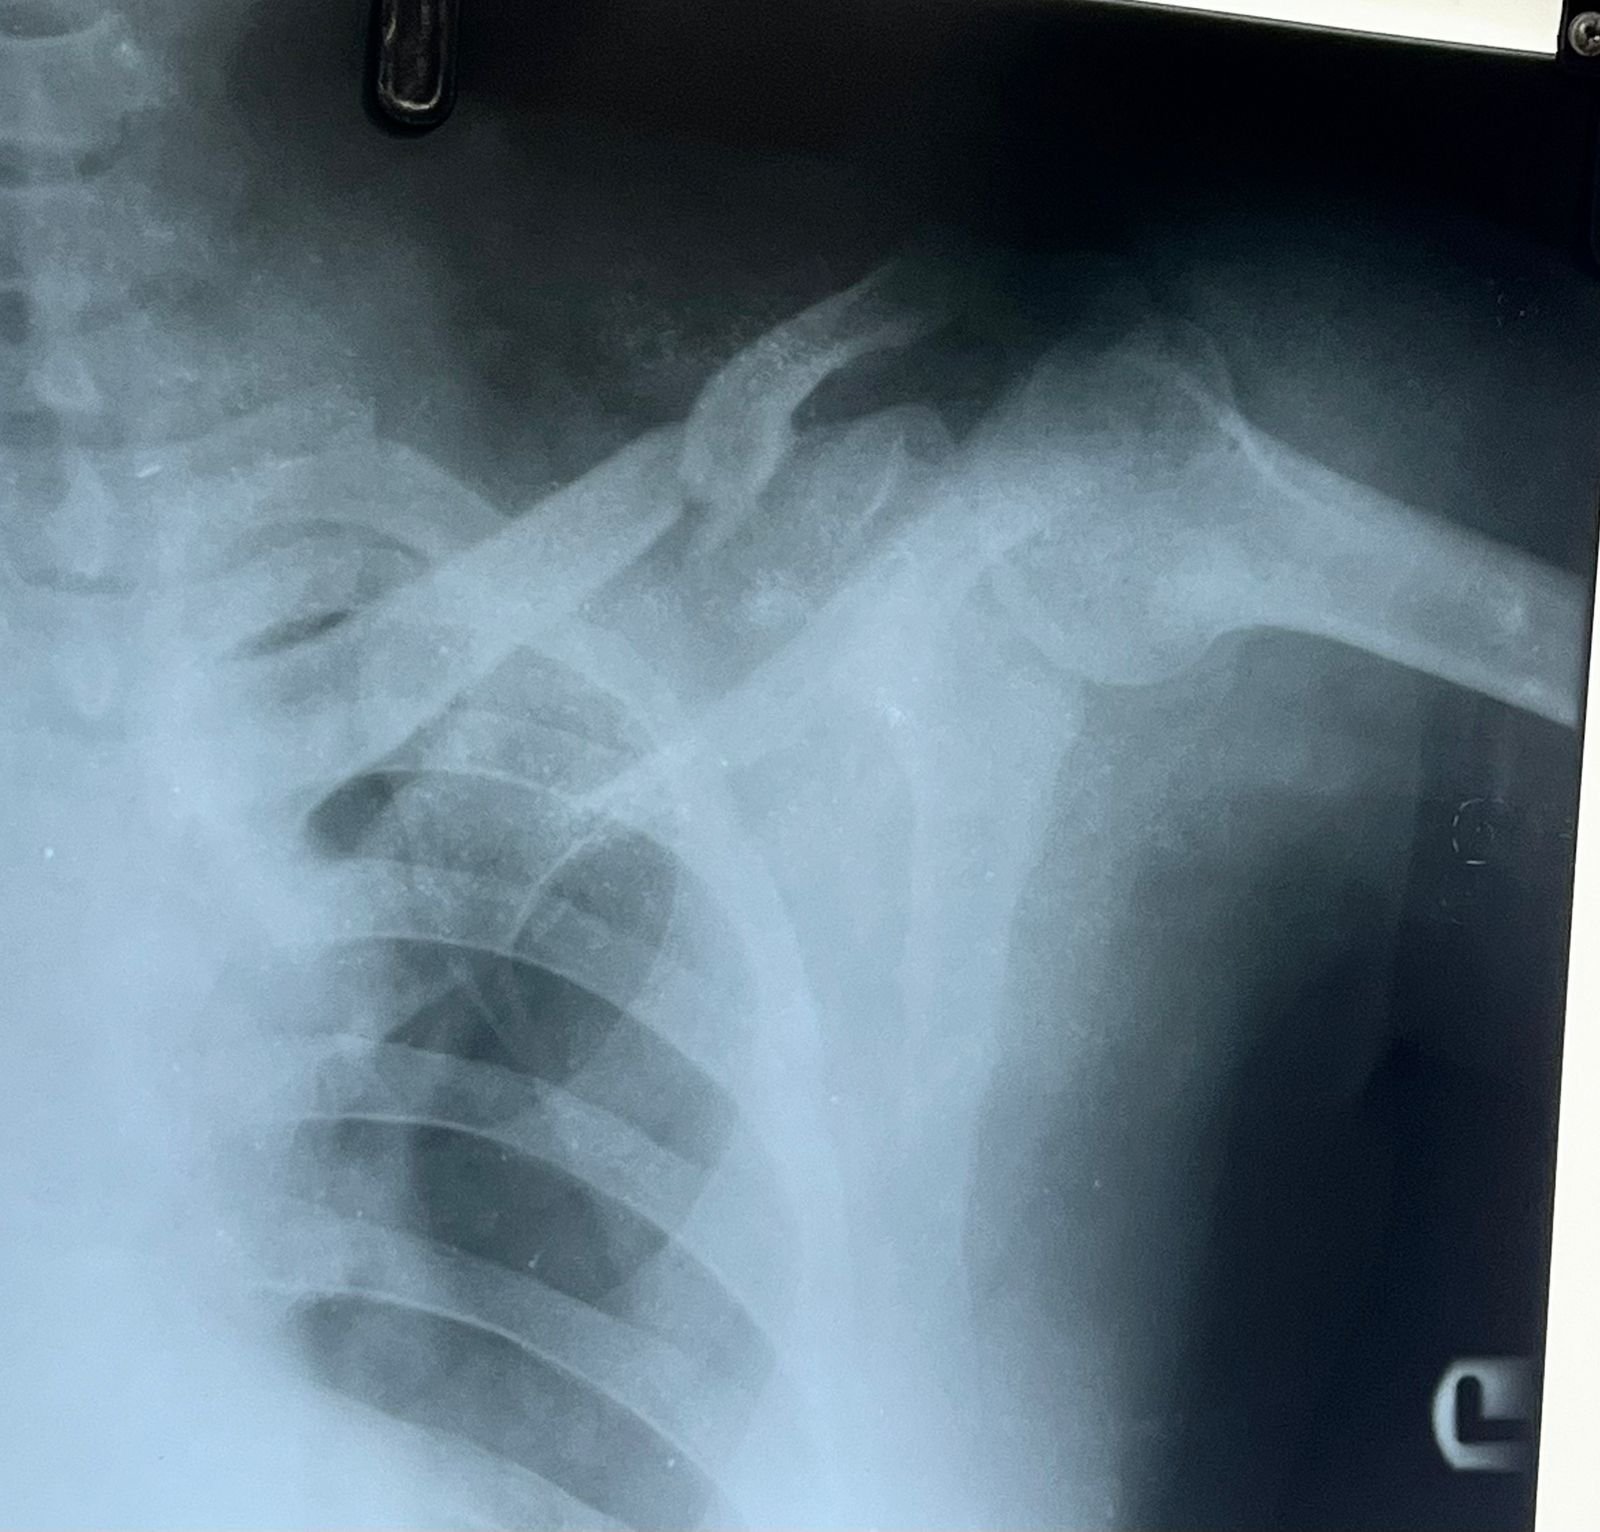

& fibula | Heal fracture pre & postop | Clavicle

fracture pre &

Heal fracture pre & postop | Clavicle fracture pre &